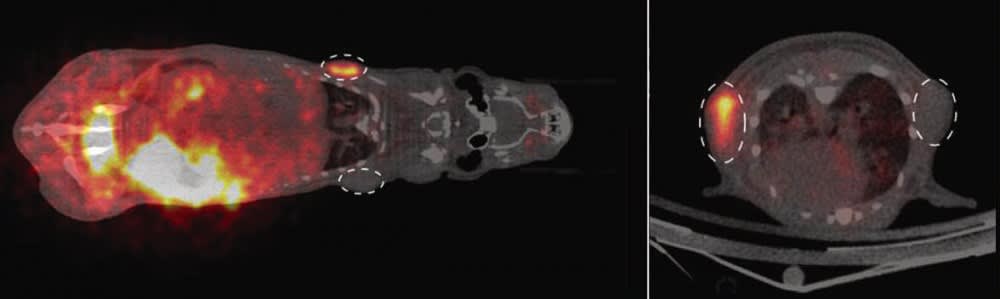

The scientists first checked whether the synthesized substrate remained stable when in contact with blood in the test tube and then examined how the cells interacted with the substrate in the first practical tests in cell cultures. In doing so, they compared human tumor cells into which they had genetically incorporated the SNAP-tag enzyme with those that did not produce the enzyme. They could see very clearly that the radioactivity was only taken up by the cells that produced the SNAP-tag enzyme. Finally, the team conducted targeted studies on individual mice because how a molecule behaves in the complex biological environment in a living organism cannot be fully simulated in cell culture or with artificially produced organs. The scientists were able to show that once the substrate is injected into the bloodstream it is distributed through the body very quickly. Additionally, they identified the pathways through which it is excreted. They then compared how tumor cells with and without the SNAP-tag enzyme reacted to the substrate in living organisms. For this purpose, the tumor cells were injected under the skin of mice and removed again after the examination in order to confirm the results with autoradiography.